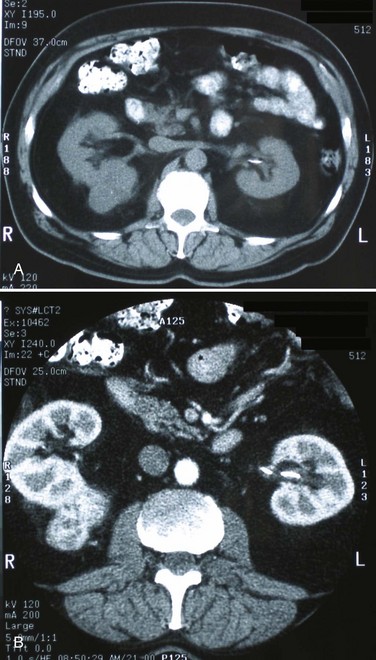

Category IV lesions have large cystic components; irregular, shaggy margins; and, most important, solid enhancing portions that provide a definitive diagnosis of malignancy (Fig. 49–8) (Bosniak, 1997; Israel and Bosniak, 2003c, 2005). Category IV lesions are almost invariably cystic RCCs that, if localized, require surgical treatment.

Figure 49–8 Bosniak class IV cysts. A, CT scan shows complex left renal cystic lesion with thick, enhancing walls. B, CT scan shows complex right cystic lesion with enhancing nodular areas and inhomogeneity. Both lesions proved to be renal cell carcinoma.